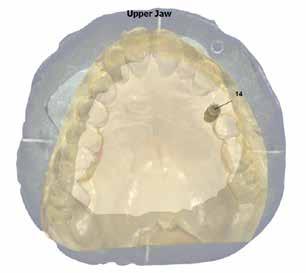

A-PRF membránokkal borítottuk (7. ábra). A mukogingivális lebenyt – annak megnyújtása nélkül – a helyére fektettük és varratokkal rögzítettük, per primam sebzárást nem végeztünk (8., 9. ábra). A varratokat 2 hét után távolítottuk el, a varratszedésig a sebgyógyulás támogatására per os 1000 mg/nap C- és 12 000 NE/nap D-vitamint adtunk (20). A műtéti beavatkozást 24 hét gyógyulási időszak követte, melynek során sem helyi, sem gyógyszeres kezelés nem történt, az esztétikum javítása érdekében a páciens ideiglenes kivehető fogpótlást használt. A csontos gyógyulás ellenőrzése és az implantáció tervezése céljából állcsonti CT felvételt készítettünk, illetve lenyomatvételt végeztünk. A CT felvételen tökéletes csontos gyógyulást észleltünk, az alveolaris csont volumene teljes mértékben megtartott volt (10. ábra), a klinikai kép is ennek megfelelően alakult (11., 12. ábra)

A Trishape Implant Studio™ a korábbi csont augmentáció területén, a felső állcsontnál áltagosnak számító D2-D3 csontminőséget jelzett (13. ábra). A lenyomat alapján készített gipszmodellt szkennelve virtuális mintát nyertünk. A CBCT felvétel és a virtuális modell adatait a Dual Scan protokoll (21) elveinek megfelelően használtuk fel az implantációs sablon (New Age Dental Kft, Nemeskéry Károly) készítéséhez (14., 15., 16. ábra). Az implantátum (Ankylos C/X A11) behelyezése teljesen navigált módon, 35 Ncm primer stabilitással történt (17., 18. ábra). Az implantátumra a fogtechnikus (D1 Dental Kft., Garamvári Csaba) által előzetesen